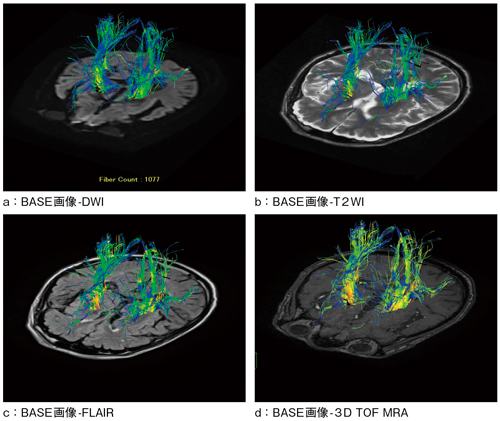

次に,本DTI解析ソフトウェアの特徴について紹介する。本ソフトウェアにはDTI解析結果に対してあらゆる画像をフュージョンすることができる(図4)。さらに,描出された神経線維の数をカウントすることができるため,これまで定性的な評価が主であったDTI解析が定量的解析に利用可能となり,これからの幅広い臨床応用に期待できると考えられる(図4 a)。

図4 異なるコントラスト画像と拡散テンソルとのフュージョン画像の応用例

診断に用いられるさまざまなMRI画像と神経線維の走行を同時に表示できるため,病変と神経線維との同定に役立つ。